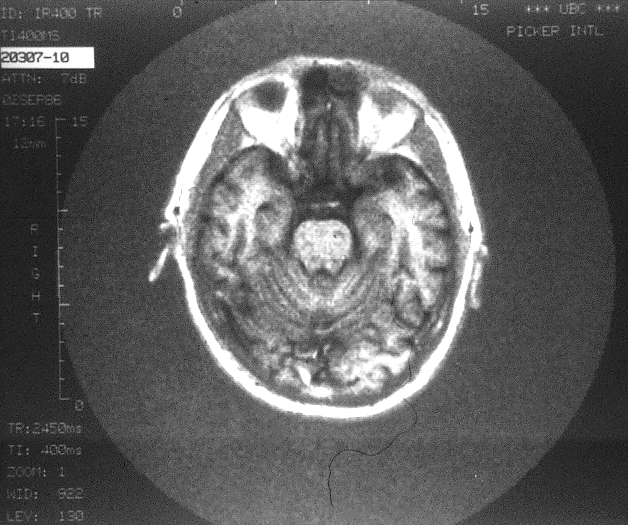

... and another one. Notice the anatomical detail in these images of the soft tissues of the brain. Even on these images, acquired in 1986, complex folds and other topological features are obvious; the state-of-the-art in NMR Imaging has advanced a great deal since then!